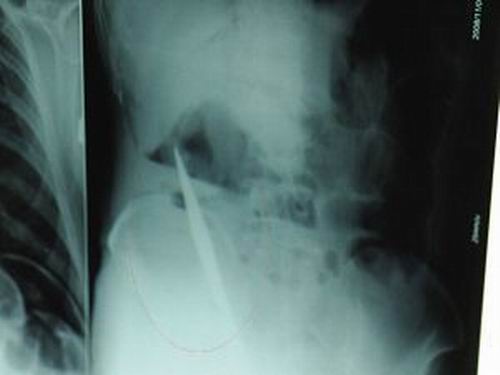

X光片上,尖刀清晰可見。

從男子體內取出的尖刀足足有19厘米長。

昨天(11月6日)上午,記者在徐州礦務集團總醫院重癥監護室見到了這名男子,目前他雖然已經恢復了意識,但還不能開口說話,需要呼吸機輔助呼吸。據醫生介紹,4日中午12時左右,這名男子因服毒輕生被緊急送到醫院進行搶救,之前,這名男子已經在當地鄉鎮醫院進行了近20小時的治療,但效果不佳。“病人被轉院到礦總院時已神志不清,血壓極低,處于休克狀態。”救護人員給男子洗胃、初步處理以后,發現男子呼吸急促,于是趕緊給他拍片檢查。結果讓所有的醫生大吃一驚,竟有一把尖狀異物橫在該男子腹腔內!當天下午5時30分,輕生男子被推上了手術臺。經過40多分鐘的手術,該男子腹腔被打開,手術醫生發現,男子體內的金屬狀異物竟然是一把長19厘米的尖刀!

醫生告訴記者,手術后,醫生在病人身上并未發現刀痕,最后,經過檢查發現,在該男子直腸處找到穿孔。醫生從醫學角度分析后認為,這把尖刀應該是從肛門插入直腸的。